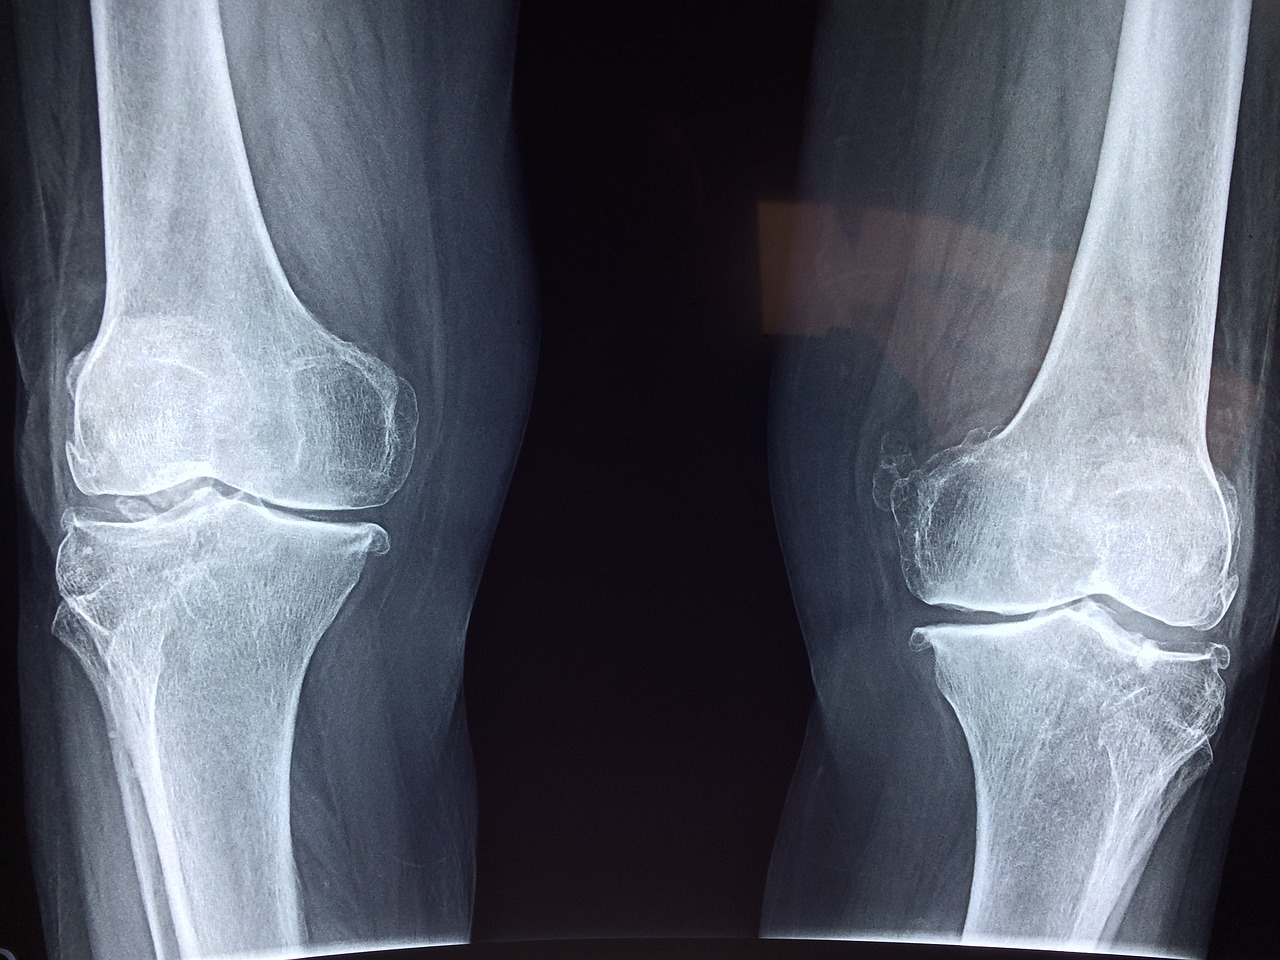

(2) 프로테오글리칸 효능- 뼈, 관절염에 효과, 염증제거

프로테오글리칸의 가장 대표적은 효능이라면 바로 뼈, 연골, 관절에 도움이 된다는 점입니다. 프로테오글리칸은 인대와 뼈, 연골에서 발견되는 성분입니다. 프로테오글리칸은 연골과 뼈의 재생을 촉진한다는 연구결과가 있습니다. 그리고 염증제거에도 효과가 있고 조직의 재생에도 효능이 있기에 프로테오글리칸을 드신다면 관절염과 뼈건강뿐만이 아니라 염증제거에도 효과가 있습니다.